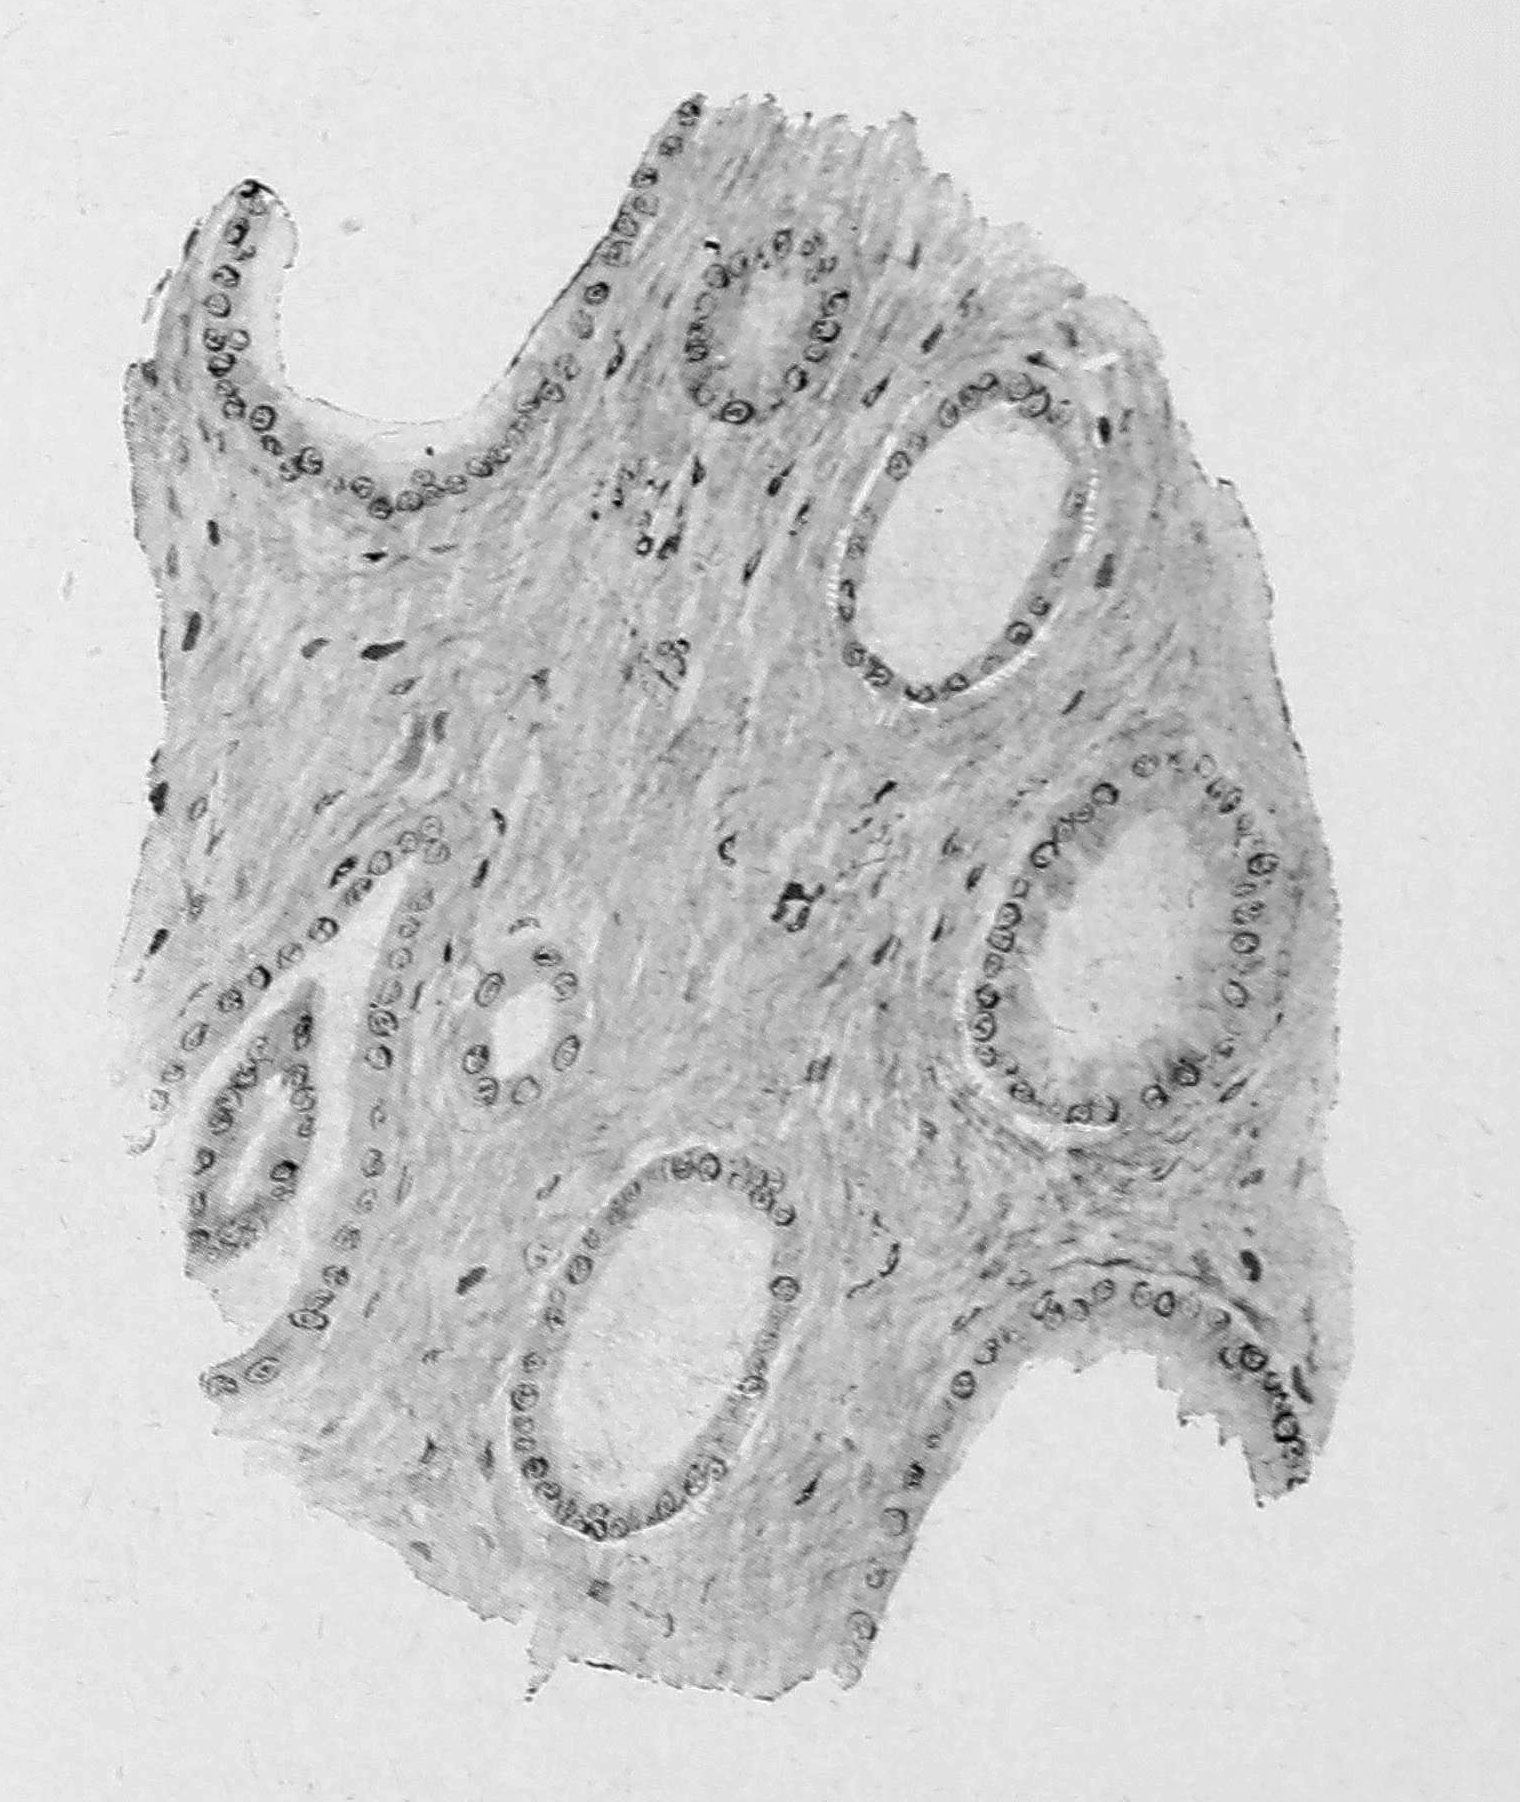

У больной была диагносцирована срощенная вследствие бывшего перекручивания кистовидная опухоль правого яичника. При операции оказалась перекрученная и срощенная правосторонняя трубно-яичниковая киста, находившаяся в интересных отношениях к левой трубе. Эта последняя, будучи свободной от срощений и имея незарощенным фимбриальный конец, была как-бы сложена вдвое в виде петли и верхушкой этой петли интимно соединялась с трубно-яичниковой кистой при помощи короткого тяжа, имевшего одинаковую с трубой толщину. Срезы показали, что этот как-бы вставочный участок в своей ближайшей к трубе части имеет довольно типичное для трубы строение, содержит просвет, выстланный слизистой оболочкой трубного характера, но с просветом трубы не соединяется. В части, прилежавшей к капсуле кисты, строение трубного просвета уже теряется, и можно видеть лишь отдельные железистые полости, покрытые цилиндрическим эпителием и местами окруженные цитогенной тканью (см. рис. 3).

Рис. 3. Железистые включения в капсуле трубно-яичниковой кисты. Zeiss, Ob. DD. Ос. III.

В этом случае наиболее вероятным представляется нам такое толкование формального и каузального генеза описанных гетеротопий: на левой трубе имелась добавочная труба, слепо соединявшаяся с главной трубой; фимбриальный конец этой добавочной трубы, благодаря воспалительному процессу, вовлечен был в капсулу опухоли и послужил источником гетеротопий. Другое возможное об’яснение, — что здесь дело идет о срощении верхушки петли сложенной вдвое левой трубы с опухолью и о последующем вростании элементов слизистой оболочки трубы, — встречает некоторое затруднение в том обстоятельстве, что с просветом трубы канал, имевшийся в толще соединительного участка, сообщения не имел.